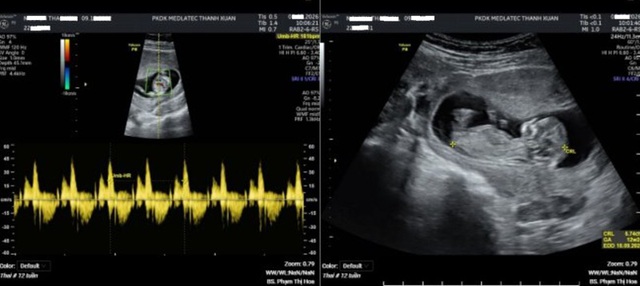

Kết quả siêu âm thai 4D cho thấy một thai phát triển tương ứng tuổi thai, tim thai 161 lần/phút, chưa phát hiện bất thường hình thái. Tuy nhiên, chỉ số PI động mạch tử cung – một thông số quan trọng trong đánh giá nguy cơ tiền sản giật – lại ở mức cao, với bên trái 2,27 và bên phải 1,67.

Đáng chú ý, xét nghiệm sàng lọc cho thấy nguy cơ tiền sản giật trước 34 tuần là 1/301 (chưa vượt ngưỡng nguy cơ cao), nhưng nguy cơ trước 37 tuần là 1/78, vượt ngưỡng 1/100. Từ đó, bác sĩ xác định thai phụ thuộc nhóm nguy cơ cao và cần được theo dõi, dự phòng sớm.

Kết quả siêu âm thai của thai phụ. Ảnh: BVCC